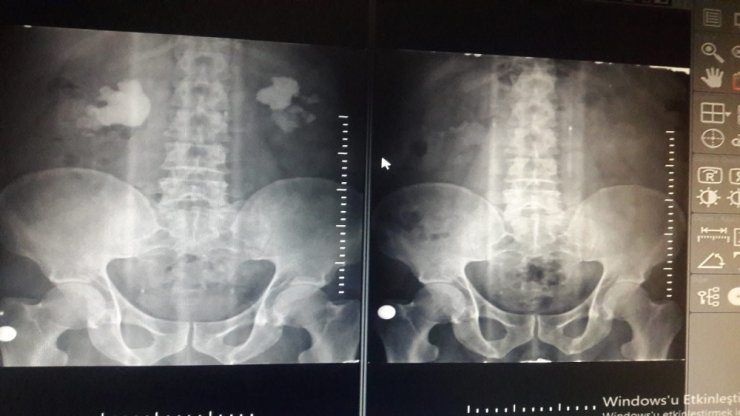

Çanakkale'nin Ezine ilçesinde ameliyat olan Cahit Erol'un iki böbreğinden 500 adet taş çıktı.

10 yıldır bel ağrısı çeken memur Cahit Erol, Ezine Devlet Hastanesi Üroloji Polikliniğine başvurdu. Bunun üzerine Erol'a yapılan kontrol ve muayene sonrası iki böbreğinde yüzlerce taş tespit edildi. Üroloji Uzmanı Muhammet Okumuş, ameliyat olmasına karar verdi. Ezine Devlet Hastanesinde kapalı ameliyat yöntemiyle yapılan operasyon sonrasında Erol'un böbreklerinden 500 adet taş çıktı. Taşların alınmasıyla Cahit Erol, sağlığına yeniden kavuştu.

Üroloji Uzmanı Muhammet Okumuş ise, "Cahit Beyin her iki böbreğinde geyik boynuzu şeklinde taşlar vardı. Bu rahatsızlıkla bize başvurdu. İdrar kanaması ve bel ağrısı vardı. Kapalı ameliyat yöntemiyle iki böbrekte bulunan geyik boynuzu şeklinde taşlar alındı. Hasta ameliyatın ikinci gününde taburcu oldu" dedi.